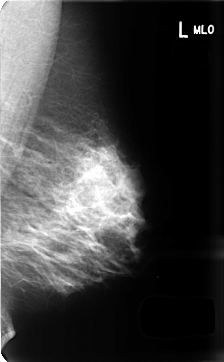

B_3436_1.LEFT_MLO

LEFT_MLO LINES 4696 PIXELS_PER_LINE 2912 BITS_PER_PIXEL 12 RESOLUTION 50 NON_OVERLAY